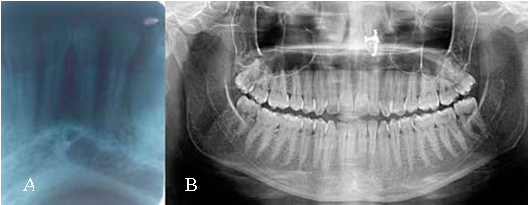

33. No discharge on palpation from growth was seen. Calculus was present between 31, 32, 33 teeth. On the basis of history & clinical examination, a provisional diagnosis gingival epulis was made. The differential diagnosis considered was traumatic firoma, pyogenic granuloma, Peripheral fibroma with calcification, Peripheral Cemento-ossifying fibroma, and Peripheral giant cell granuloma. The intraoral periapical radiograph 31, 32, 33, 41 and orthopantomographic (OPG) examination showed no obvious bony changes. (Figure 2 a & b). All the hematological reports were in normal limits. Later with patient consent, excision of the lesion was done under local anesthesia (Figure 3) and the specimen was sent for histopathological examination, which showed parakeratinzed stratified squamous epithelium of variable thickness with evidence of ulceration in some areas. The underlying dense fibrous connective tissue shows varying degrees of cellularity along with foci of mineralization. The hard tissue component showed basophillic acellular spherules. There was presence of focal chronic inflammatory cell infiltrate and granulation tissue formation in some areas. These features were suggestive of peripheral cemento-ossifying fibroma. (Figure 4) In the present case, after excision of the lesion, all the remnant of the lesion was removed and thorough debridement was done. Capsule amoxicillin (500mg), tablet metronidazole (400mg) and tablet ibuprofen (400mg) were prescribed to the patient thrice daily for five day postoperatively, to relieve the pain and to prevent secondary infection Following this, close monitoring was done after 10 days, 1 month, 3 months and 6 months and no recurrence was observed. The surgical site appeared to be healing well. The patient was asymptomatic, aesthetically sound and satisfied with results on follow up.

Radiographically, PCOF may follow different patterns depending on the amount of mineralized tissue, radio-opaque foci of calcification have been reported to be scattered through the central area of the lesion, but not all lesions exhibit these radiographic characteristics. Most lesions are not associated with bone destruction. In rare instances, superficial erosion of bone is noted (5,8). Radiographic finding were non-contributory in the present case. Histologically, the lesion appears as non- encapsulated fibrous connective tissue with parakeratinzed stratified squamous epithelium of variable thickness with evidence of ulceration in some areas. Benign fibrous connective tissue with varying content of fibroblasts, myofibroblasts and collagen, sparse to profuse endothelial proliferation, mineralized material which may represent mature, lamellar or woven osteoid, cementum like material or dystrophic calcifications. Acute or chronic inflammation related findings can also be identified in lesions (5). Most of these features were reported in present case. This emphasizes the need for histopathological examination of biopsy specimen for an accurate diagnosis because of difficulty in diagnosing PCOF based only on clinical and radiographical observation.